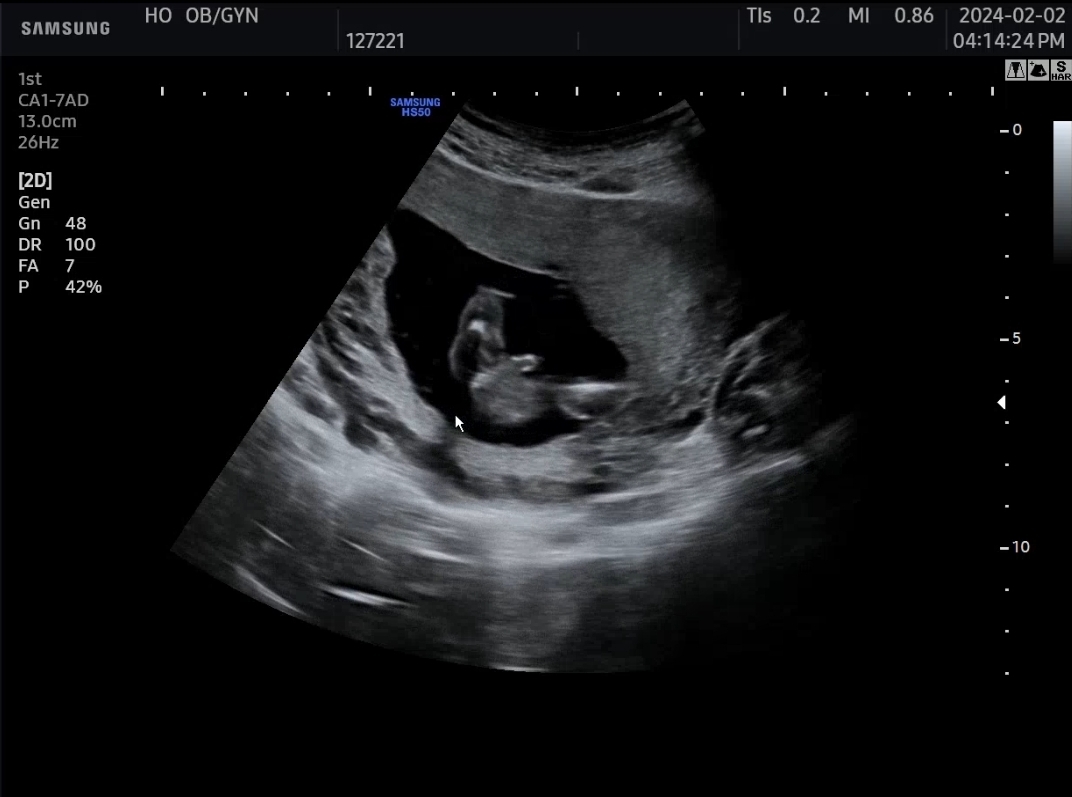

16주 초음파 성별이요!

첫째도 아들인데 딱 봐도 둘째도 아들 맞죠..?ㅎㅎ

나 아들이다아!!! 하고 뙇 보여주는거 같아요ㅎㅎ

다리가 너무 유연하게 잘 벌어지네뇨!!!!!아들!!!!